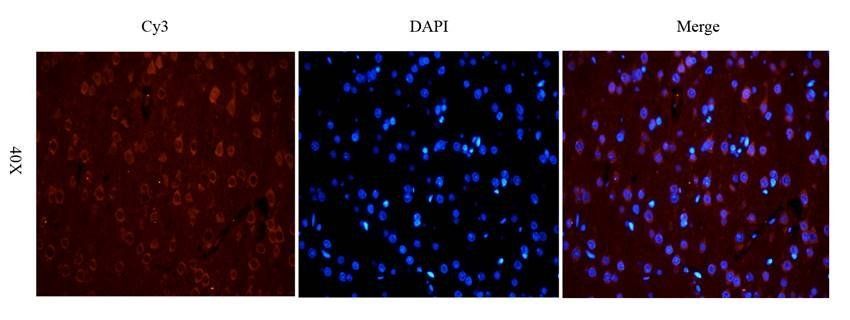

100 μg - FOXP3 antibody [orb34127]Featured

ELISA, ICC, IF, IHC-P, WB

Human, Mouse, Rat

Rabbit

Polyclonal

Unconjugated

100 μg - OPG antibody [orb247239]Featured